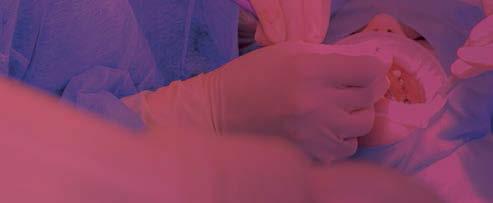

Este parámetro se puede obtener en el propio sillón dental mediante punción capilar, para lo cual se desinfecta el pulpejo del dedo y se obtiene una pequeña gota de sangre con una lanceta. Posteriormente se procesa la gota mediante un sistema portátil y desechable estandarizado (Figura 8)

El procedimiento se realiza de forma sencilla y en unos minutos siguiendo las instrucciones del fabricante. De esta manera,

se obtiene un porcentaje de hemoglobina glicada, que es indicativo de la posible presencia de patología (Tabla 4) y cuya correspondencia con los niveles de glucemia se expone en la Tabla 5 Es necesario resaltar de nuevo que esta prueba en el gabinete dental es indicativa pero no diagnóstica de prediabetes o diabetes.

Determinación de la situación glucémica. Test de hemoglobina glicada

El control de la glucemia se evalúa principalmente con la prueba A1c, que fue la medida estudiada en los ensayos clínicos que demostró mayor eficacia en este sentido. A los pacientes con un riesgo moderado de diabetes según el cuestionario FINDRISC (puntuaciones ≥12) se les realizará un examen de la hemoglobina glicada (HbA1c). Esta prueba mide el porcentaje de la hemoglobina de los glóbulos rojos cubierta de glucosa (glicada) reflejando el promedio de los niveles de azúcar en la sangre de los últimos tres meses. Se realiza utilizando sangre de punción digital analizada con un dispositivo portátil (A1CNow+®, Bayer Healthcare, Leverkusen, Alemania). Esta prueba ha sido certificada tanto por el Programa Nacional de Estandarización de Glicohemoglobina (NGSP) como por la Federación Internacional de Química Clínica y Medicina de Laboratorio (22).